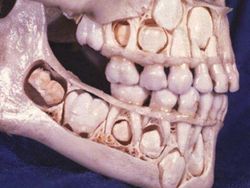

Tengkorak anak sebelum gigi susu tanggal Foto: Boredpanda